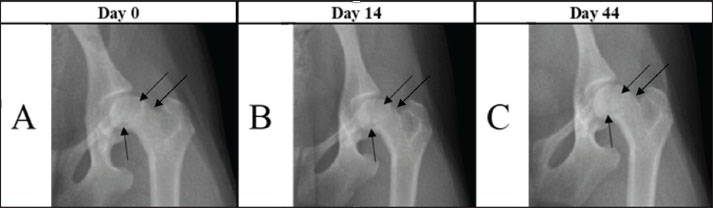

Radiographic examination (EcoRay 400, Germany): The hips were radiographically assessed using an extended ventro-dorsal projection (Fig. 1). The severity of LCPD affecting the hip joint was graded according to the Ljunggren classification scale (Ljunggren, 1967).

Fig. 1. Images showing reduction in femoral head and neck lysis on days 0, 14, and 44. Radiographs A and B show a decrease in the radiopaque contrast of the bone tissue (black arrows). In C, the same bone areas are homogeneous compared with other bone regions.

The case involved an 11-month-old female Toy Poodle weighing 2.5 kg. The owners reported observing hindlimb lameness for approximately 1 month. Despite the previous treatment with oral meloxicam suspension (Melosus 1,5 mg/ml, CP-Pharma Handelsgesellschafts mbH, Germany) at 0.1 mg/kg for 3 weeks, the left hindlimb lameness did not improve. Upon clinical examination, the dog exhibited lameness in the affected limb, thigh muscle atrophy, hip joint crepitus, and painful flexion and extension movements. Radiographic examination confirmed grade 1 LCPD according to the Ljunggren scale (Ljunggren, 1967). On the Day-1 radiograph, there was a reduction in bone density (focal lysis) in the femoral head (Fig. 1A), and the distal margin of the femoral neck was not clearly delineated. 14 days after the PRP injection, follow-up radiographs showed diminished femoral-head lysis, but the head itself had become markedly irregular (Fig. 1B). The distal border of the femoral neck was now distinguishable. In Chinnabrut’s 2022 study, surface deterioration of the femoral head was likewise noted in two of the three cases, although the control radiographs were taken only at 8 weeks. Parra and Silva (2017) study reported a similar worsening of the femoral head surface as early as 15 days post-treatment, and this change persisted throughout the study. By day 44, the bone lysis had stopped, and the distal outline of the femoral neck was still clearly defined (Fig. 1C). In addition, the mild surface irregularity previously seen on the femoral head was partially resolved. In Chinnabrut’s 2022 study, one of the three cases exhibited no femoral head changes; however, radiographs were obtained only twice, in the first 24 hours and again at 8 weeks, so it is impossible to determine whether a transient surface deterioration similar to that observed here developed and later subsided in the interim. Clinically, lameness improved significantly by day 14, although muscle atrophy persisted, and hip flexion and extension pain-free ROM increased. By day 44, lameness had completely resolved, muscle atrophy had ceased with evidence of muscle regeneration, and both hip flexion and extension were pain-free (Table 1). Chinnabrut and Soontornvipart (2022) reported that lameness resolved in two of three dogs and improved in the third by eight weeks posttreatment. In contrast, Parra and Silva (2017) reported a transient worsening at Day 15, followed by full resolution by Day 30. These findings align with our own results, in which we documented significant clinical improvement—including resolution of lameness—was documented by Day 44. Collectively, the evidence suggests that measurable clinical benefits after intraarticular PRP may require at least 30 days to become apparent. The transient inflammation and pain seen after PRP administration may stem from proteins released by platelet α-granules: these proteins up-regulate inflammatory receptors that enhance platelet adhesion to other cells and release multiple chemokines (Blair and Flaumenhaft, 2009). Hip-joint range of motion improved in both the Chinnabrut and Soontornvipart (2022) and Parra and Silva (2017) series, although direct comparison is impossible because different scoring systems were used. Thigh-girth measurements in this case showed progressive muscle-mass gain from day 1 to day 44, despite a transient setback on day 14. Similarly, Chinnabrut and Soontornvipart (2022) recorded increased thigh muscle mass in two dogs that became sound, whereas the dog with residual lameness exhibited no muscular improvement.

The owners observed a notable improvement as early as 3 days following the initial PRP injection, an outcome not previously achieved with nonsteroidal anti-inflammatory drug treatment. Intraarticular PRP injections successfully alleviated pain and resolved lameness over the 44-day study period. No adverse effects were observed. The improvement in lameness was confirmed by increased ROM and thigh girth measurements. Although the radiographic changes on day 14 were not considered significant, clinical improvement was evident. By day 44, radiographs revealed halted lysis and increased bone tissue density (Fig. 1C). Similar observations of radiographic changes alongside clinical improvement were noted by Chinnabrut and Soontornvipart (2022).